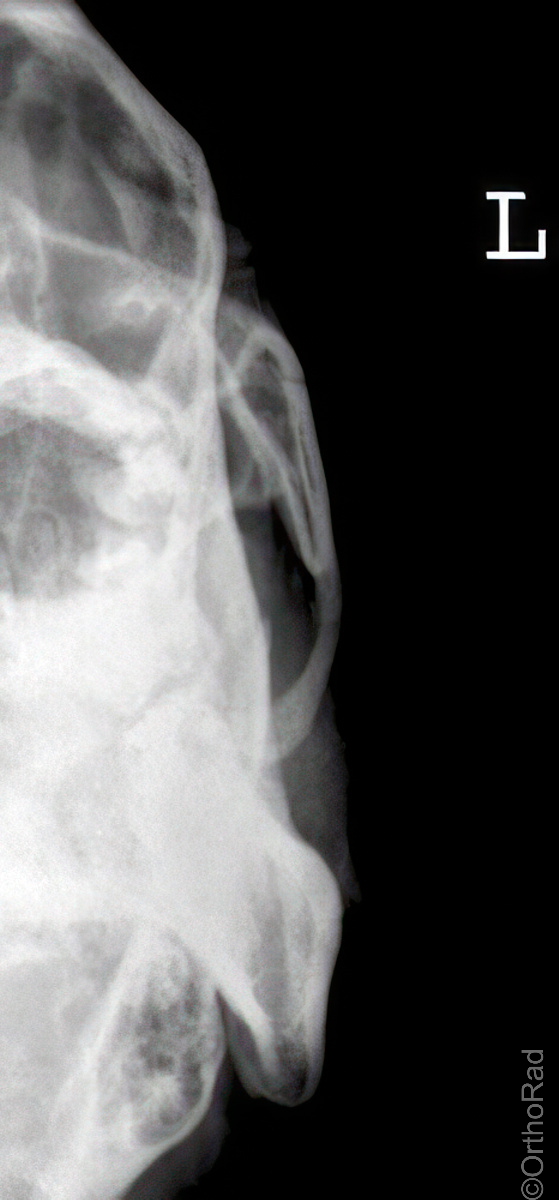

Schädel lateral

Technik

• FDA: 1,15 m

• Ausgangsformat: 24/30

• mit Raster

Indikation

Fremdkörper-Lokalisation vor MRT, Shuntventil-Kontrolle

Lagerung

Schräg-Bauchlage mit aufstützender Hand der anliegenden Schädelseite

Beine leicht angezogen

Kopf streng seitlich

Medianebene parallel zum Tisch

Kinn und Stirn auf einer gedachten Linie (D.-H. nicht relevant)

Zentralstrahl

Querstrahl & Längsstrahl: ergibt sich

Einblendung

auf Haar- und Haugrenze (Nase darf abgeschnitten sein)

Qualitätskriterien

Vollständige Darstellung des gesamten Schädels, weitgehend deckend der Konturen, vordere und hintere Schädelgrube, Orbita, Kieferhöhlen und Jochbein. Zudem deckungsgleich von kleiner Keilbeinflügel und äußerer Gehörgang. Strichförmige Abbildung der Sella turcica.